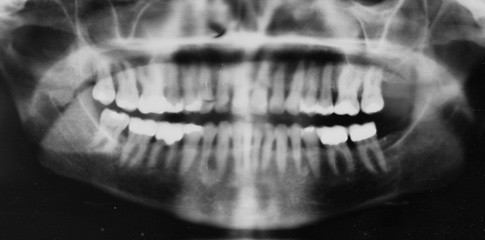

The American Dental Association has estimated that 80% of American adults have periodontal disease, including gingivitis.